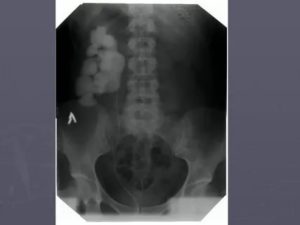

При проведении УЗИ или рентгена почек диагност может обнаружить структурные изменения в мочевыделительных органах. И каждому из них есть своё объяснение. Но при этом многие пациенты всё же интересуются затемнением в почке что это может быть.

Затемнение в почках

В основном затемнения (гипоэхогенность) могут быть по таким причинам:

- Наличие абсцесса;

- Доброкачественная опухоль;

- Возможное кровоизлияние;

- Онкология небольшого размера.

- Почечные пирамидки также имеют низкую эхогенность и могут быть тёмными на УЗИ.

Совсем черный оттенок имеют:

- Киста;

- Расширенная лоханка, переполненная мочой.

О чем говорит затемнение в почке?

Применительно к инструментальной диагностике термин «затемнение» используется в рентгенологии. В эхографическом описании структуры, которые выглядят темнее окружающих тканей, называют «гипоэхогенными» или «сниженной эхогенности». Совсем черные структуры называют «анэхогенными».

Гпоэхогенными участками могут быть следующие изменения:

- абсцесс;

- опухоль;

- кровоизлияние;

- кроме того, нормальными гипоэхогенными структурами в паренхиме являются пирамидки.

Полностью черными, «анэхогенными» могут быть: кисты и расширенные лоханки или чашечки в результате задержки оттока мочи.